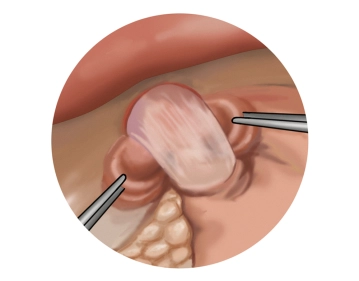

Präparation des unteren Ösophagus

![Präparation des unteren Ösophagus]()

Toneinstellungen Man geht nun weit ins untere Mediastinum hinein und löst den unteren Ösophagus zirkulär aus seinen Verklebungen heraus. Dabei wird der hintere Vagusnerv eindeutig identifiziert und verbleibt an der Ösophagusmuskulatur. Der Ösophagus wird so weit aus dem Mediastinum heraus gelöst, bis der Bereich des unteren Ösophagussphinkters spannungsfrei im Bauchraum zu liegen kommt.